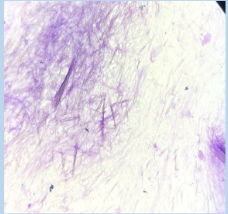

The joint fluid was aspirated and sent for microscopy which showed needle-shaped MSU crystals.

(Image 2) MSU crystals under the microscope

Synovial fluid aspiration showed needle-shaped MSU crystals.

(Image 5) MSU crystals